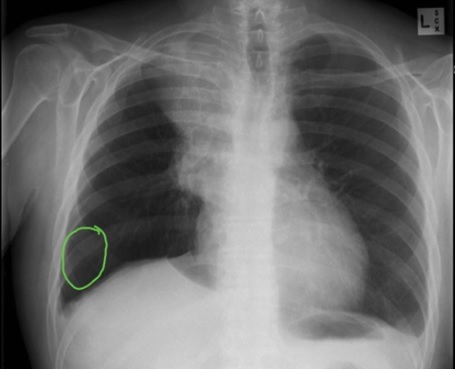

?Type of lung cancer

-Central airways

-Smokers

-Rapid doubling time

A

Small cell lung cancer